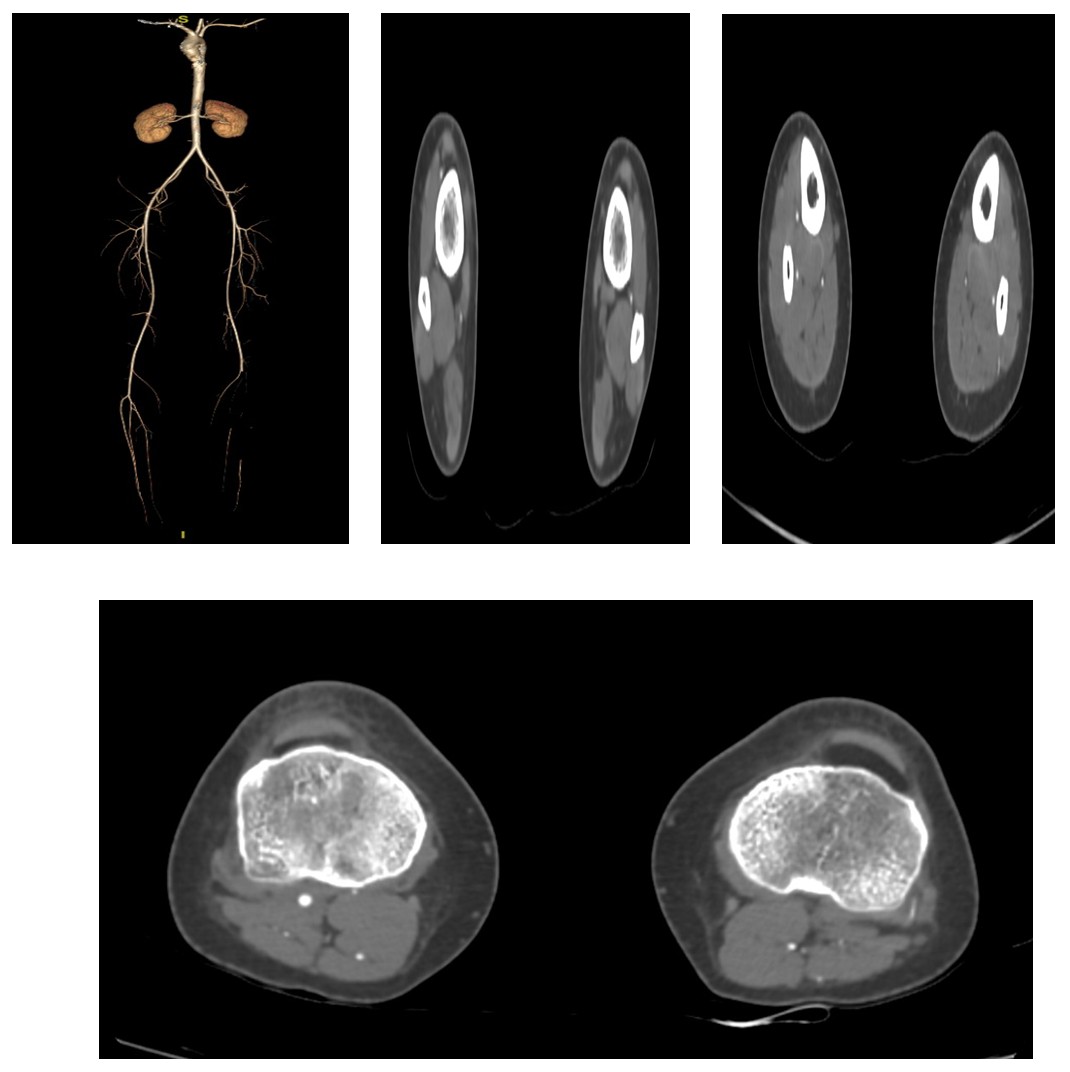

A CT Peripheral Angiogram showed

- Thrombosis involving the left proximal popliteal artery, complete occlusion with multiple thin collaterals

- No demonstrable reformation of distal arteries

- Additionally, findings suggested right lower lobe pneumonitis with minimal pleural effusion and basal atelectasis.

Based on clinical and imaging findings, she was diagnosed with Acute Limb Ischemia, Left Lower Limb (Intrahospital Occlusion, Rutherford Class 2A, provoked type).